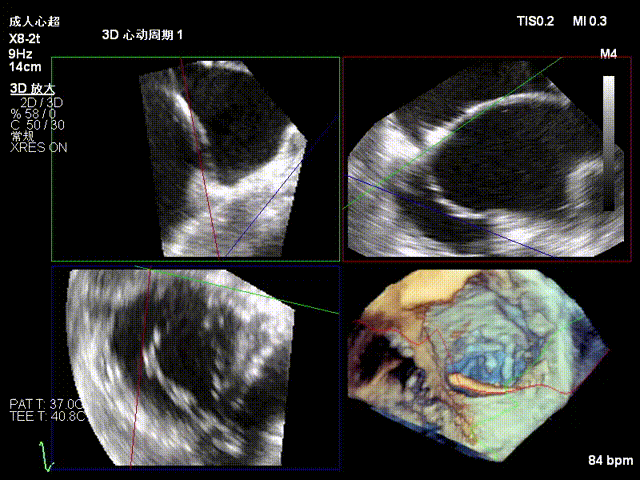

2.Annuloplasty Effect: Annular morphology remodeled, central gap significantly reduced.

Preoperative 3D

Postoperative 3D